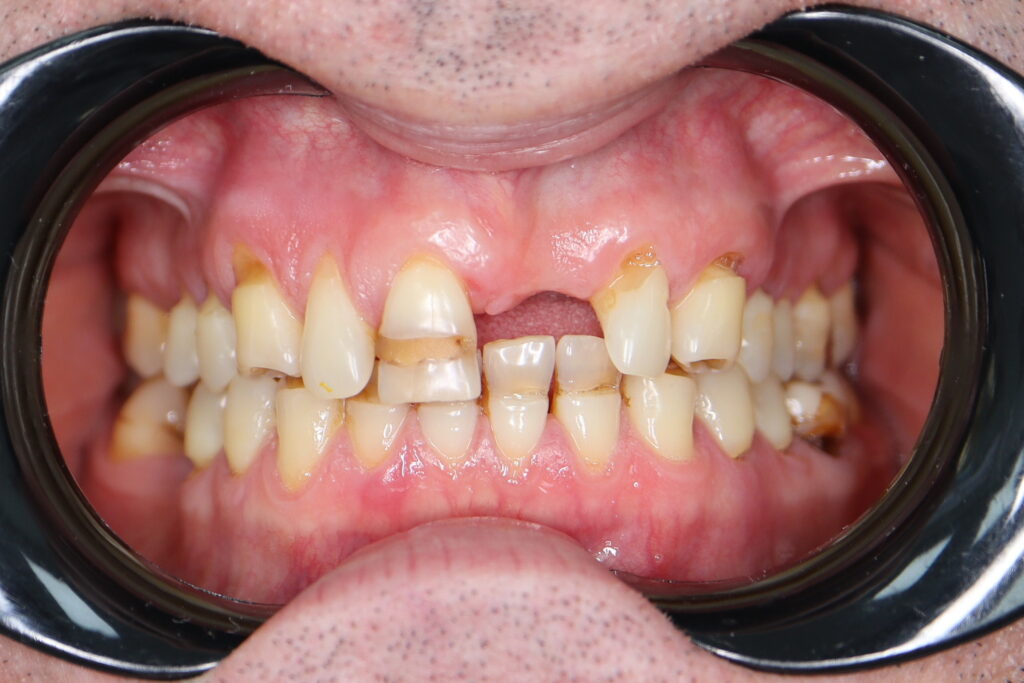

Ситуация до лечения

Пациент обратился с жалобами на эстетические недостатки.

Диагноз: Частичная адентия, клиновидные дефекты, гипоплазия эмали.

пациент до имплантации